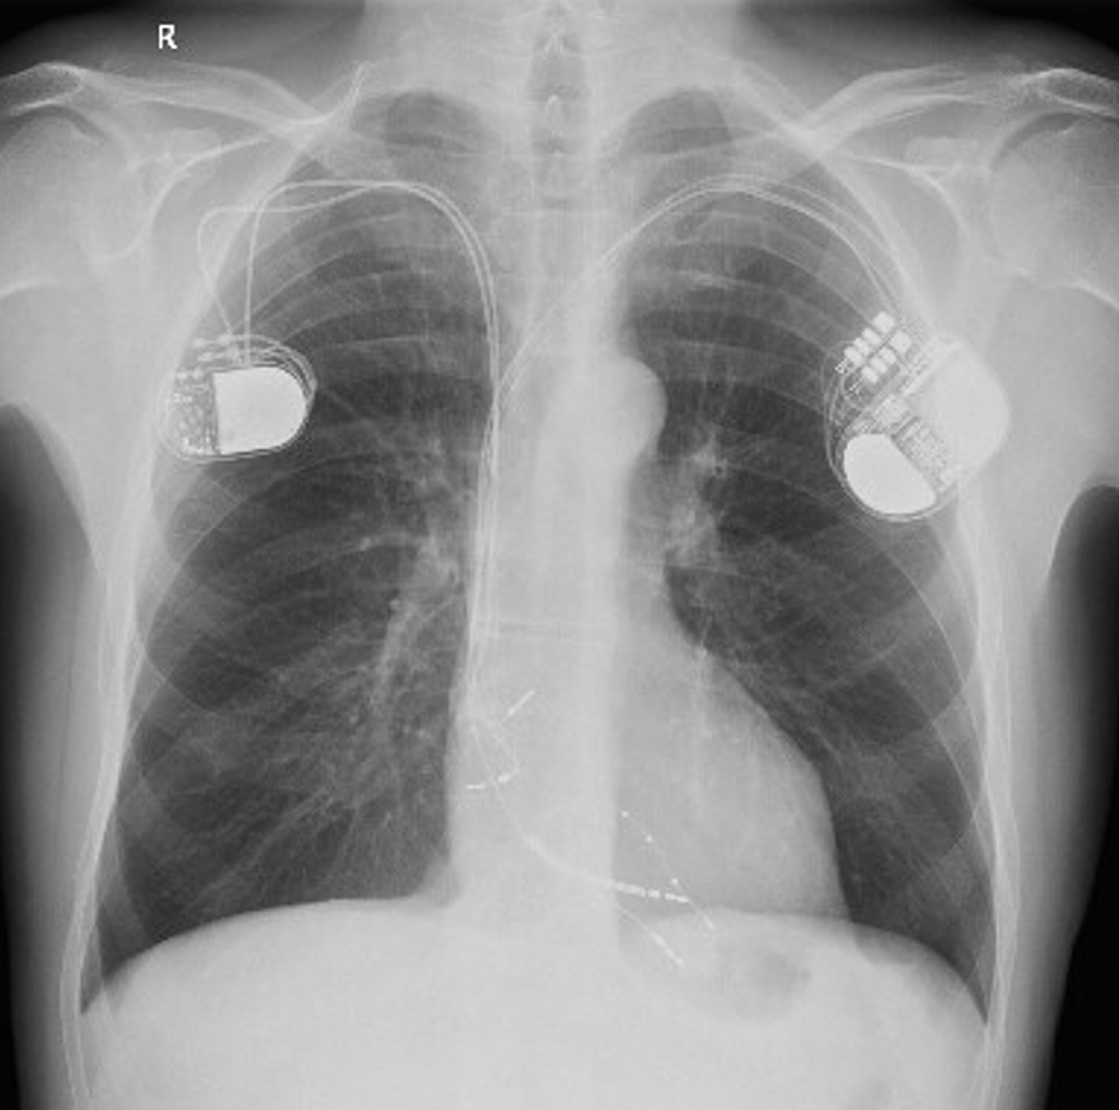

Obr. 2. Transmitrální toky při běžící komorové tachykardii.

Komorová tachykardie na EKG s frekvencí 185/minutu tak byla docela překvapením. Pacient byl hospitalizován, laboratoř neukázala zásadní patologii, v krátké anestezii byla provedena kardioverze. Ultrazvuk srdce prokázal poruchy kinetiky levé komory podobnou předchozí době, posttachykardicky ale byla ejekční frakce 35 %. Byla doplněna kontrolní koronarografie, znovu s negativním nálezem. Stávající stimulační systém byl ponechán in situ a byl přidán zleva resynchronizační systém včetně defibrilátoru a domácího monitoringu. Stranou nezůstala ani farmakologická terapie. Pacient dostal 12,5 mg spironolaktonu, 20 mg furosemidu a pochopitelně beta-blokátor: retardovaný metoprolol v dávce 25 mg. Systolický tlak při této medikaci nepřesáhl 105 mm Hg s polohovou nejistotou vždy jen ráno a po rychlém postavení. S touto terapií byl propuštěn. V ambulantní péči byl pacient stabilní, bez výboje, dle monitoringu z přístroje nebyly zachyceny komorové tachykardie. Přes výše uvedené hraniční tlaky byla s opatrností měsíc po dimisi zahájena terapie sacubitrilem/valsartanem v úvodní minimální dávce 24/26 mg dvakrát denně a přes přechodné cca týdenní období s měřenými hodnotami krevního tlaku 95/55 mm Hg se tuto terapii podařilo udržet, pacient se tlakově stabilizoval. Nedošlo k poklesu renálních funkcí ani k hyperkalémii. Pacient se vrátil k obvyklé bohaté pracovní činnosti, denně 45 minut plave. Na podzim 2021 byl ke stávající terapii přidán i empagliflozin, který pacient rovněž dobře toleruje. Furosemid užívá v režimu 1–2× týdně 20 mg, ostatní terapie zůstala nezměněna.